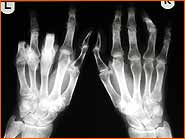

- Chronische Polyarthritis (Rheumatoide Arthritis)

- entzündliche Erkrankung der Synovialis von Sehnenscheiden, Gelenken u. Schleimbeuteln

- Gelenke u. Sehnenscheiden der Hand sehr häufig betroffen

- führt unbehandelt oft zu schwersten Funktionseinschränkungen der Hand